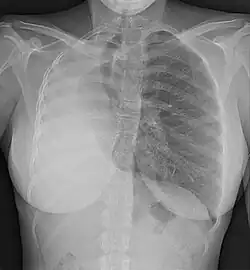

- Los pulmones, frecuentemente como consecuencia de oligohidramnios durante la gestación o por la existencia de hernia diafragmática congénita